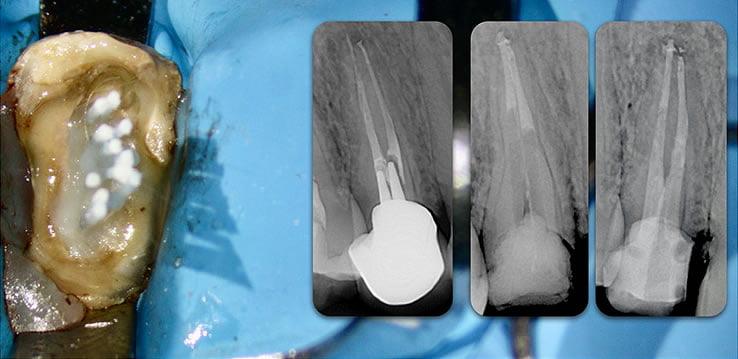

Peripheral reinforcement

- Peripheral reinforcement with the Biolight® DRILL-FREE multi-post system offers a superior resistance to mechanical stresses, when compared to a central post.

- Traditional engineering reinforcement concepts have long-established a reliance on peripheral over central reinforcement.

YES. Biolight® DRILL-FREE provides a solid, anatomical anchoring to remaining tooth structure. By arranging reinforcement towards the periphery of the canal walls, support of the core is improved. The concept is similar to how reinforcement steel rods and used in concrete structures, where many smaller rods are placed around the perimeter of the concrete. In addition, all risks associated with drilling are eliminated.